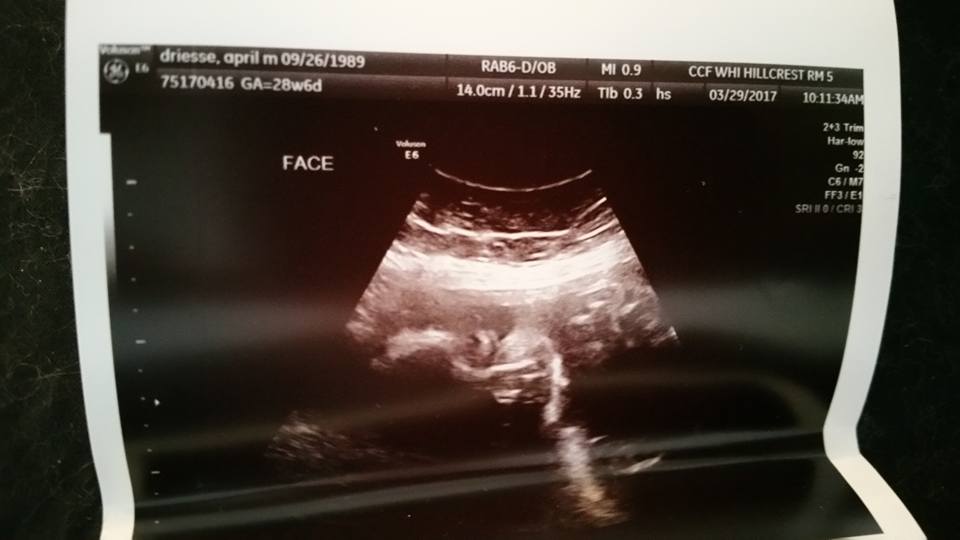

(heres a photo for tomorrow; a day early :P Shhh)

Growth Scan - March 29 2017

I had my 28 week Growth Ultrasound with Dr. Perni; Everything looked perfect as could be. I saw 4 chambers in a beating heart, and I got to see his face close and personal with a 3D Imaging of it. He was measuring 2lbs 15oz at 28 weeks 6 days. Perfect in every way. I cried.